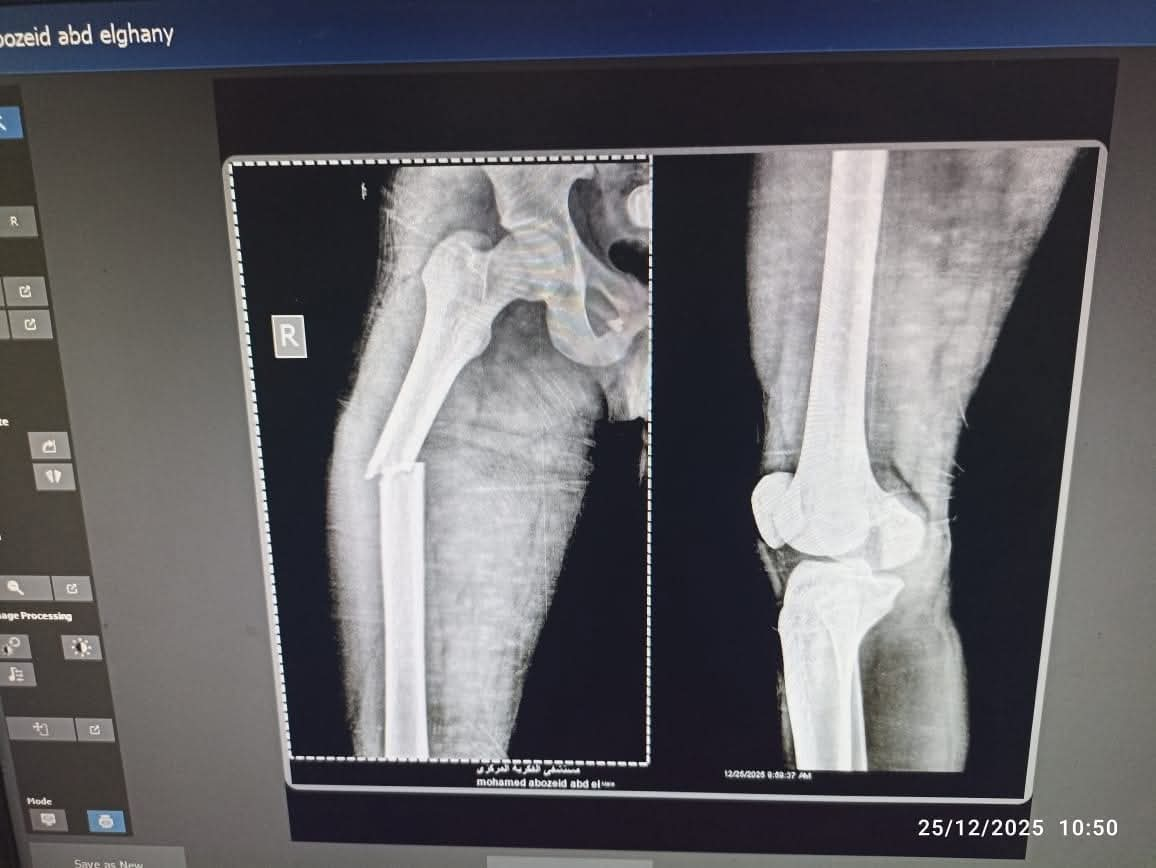

استقبل المستشفى شاباً في مقتبل العمر يعاني من إصابة شديدة ناتجة عن حادث سير، وبالفحص الطبي تبين وجود كسر في عظمة الفخذ، وهي من الإصابات التي تتطلب تدخلاً جراحياً دقيقاً لإعادة المصاب لممارسة حياته الطبيعية وتجنب أي مضاعفات حركية مستقبلاً.

قرر الفريق الطبي استخدام تقنية المسمار النخاعي التشابكي (Interlocking Nail)، وهي من أحدث الطرق العالمية في علاج كسور العظام الطويلة، حيث توفر استقراراً فورياً للكسر، وتسمح للمريض بالبدء في التماثل للشفاء والحركة في وقت قصير جداً مقارنة بالطرق التقليدية.